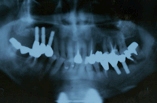

◎初診時の状態 ・右上の奥歯がぐらついて、入れ歯が入れにくい ・入れ歯で噛むと痛む ◎患者様の希望 ・上の入れ歯がかさばるので、インプラントをしてもらいたい |

| 【治療内容】 上のぐらついた歯を抜歯し、歯ぐきの状態が安定した後に手前の無い2本と共にインプラントを入れました。 その後、左下の奥歯も歯周病で噛めない箇所があったため、抜歯後インプラント、前装クラウンを右上、左下共に装着しました。 |